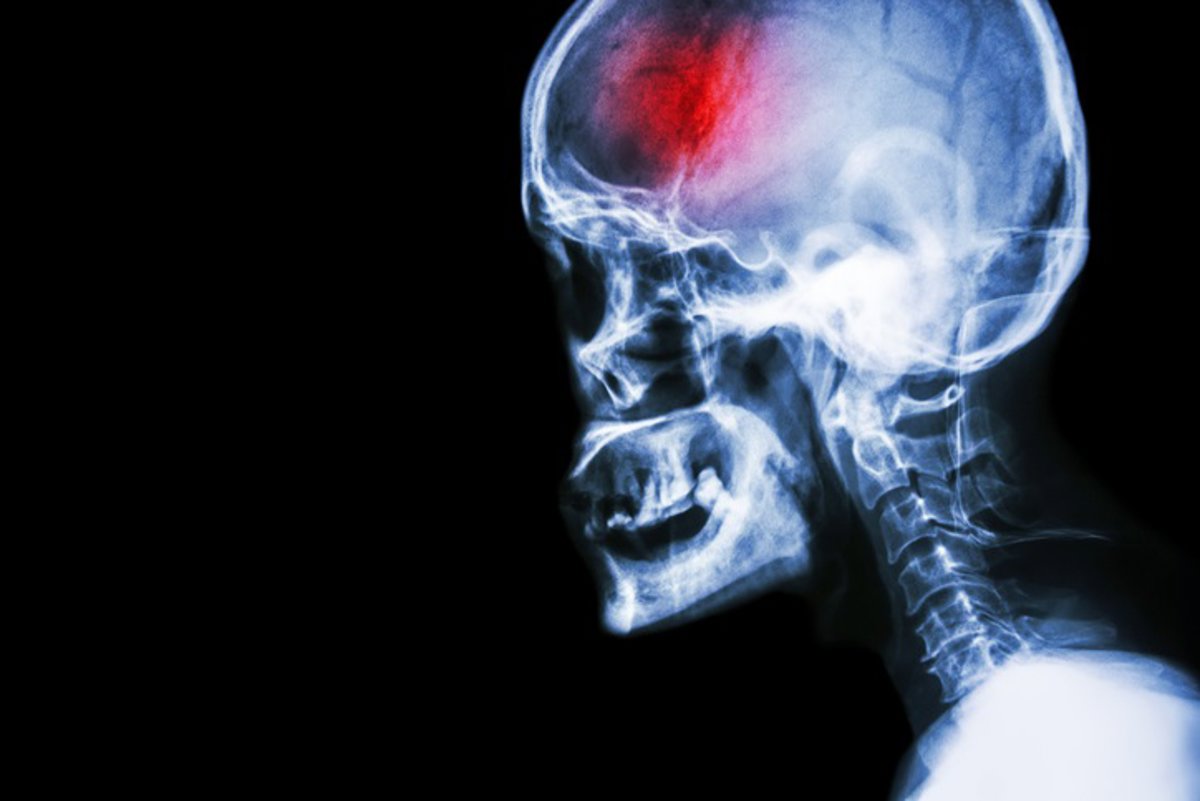

Ictus lacunar: sus secuelar pueden confundirse con efectos de envejecimiento y pasar desapercibidas

Desde la Unidad de Rehabilitación Neurológica del Hospital Vithas Xanit Internacional, un espacio de referencia que sigue el modelo de excelencia desarrollado por Irenea --el Instituto de Rehabilitación Neurológica de Vithas--, advierten de que las secuelas de un ictus lacunar, un tipo de accidente cerebrovascular de menor tamaño, pueden confundirse con los cambios asociados al envejecimiento.

Estos ictus, aunque discretos, pueden manifestarse mediante síntomas como dificultades para mover brazos o piernas, problemas para hablar o tragar, o alteraciones en la memoria y el estado emocional.

UN ICTUS PEQUEÑO PERO POTENCIALMENTE PELIGROSO

"Aunque el ictus lacunar no suele causar los síntomas más evidentes de un ictus mayor, puede ser más peligroso de lo que parece. Afecta a las pequeñas arterias de las zonas más profundas del cerebro, y está relacionado con la hipertensión crónica, el tabaquismo y la diabetes. Sus síntomas más sutiles pueden pasar desapercibidos durante mucho tiempo, dificultando el diagnóstico y retrasando un tratamiento que podría evitar mayores daños", ha agregado Enrique Noé, director de investigación de Irenea y neurólogo miembro del Instituto de Neurociencias Vithas.

A diferencia de los ictus isquémicos corticales, que suelen estar causados por un coágulo sanguíneo grande, el ictus lacunar se produce por la obstrucción de pequeñas arterias que irrigan zonas del cerebro más profundas, y en donde la zona afectada es menos amplia. Esto puede dar lugar a déficits neurológicos que no siempre son fáciles de identificar, pero que afectan la vida diaria del paciente.

Belén Moliner, directora médica del Instituto de Rehabilitación Neurológica de Vithas, ha explicado que "el ictus lacunar puede provocar síntomas como hemiparesia, alteraciones sensoriales o dificultades en el habla, alteraciones cognitivas y cambios en el carácter. Aunque estos síntomas no siempre son evidentes y aparecen en mayor o menor intensidad, su impacto en la vida diaria de los pacientes es considerable".